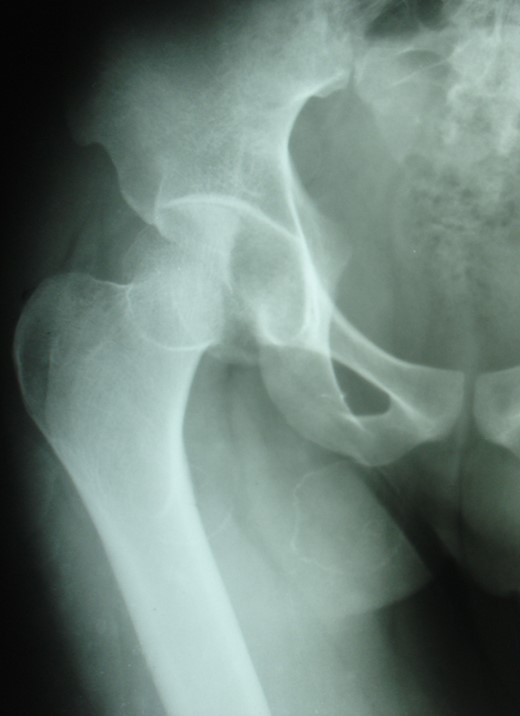

Blood parameters were within normal limits. X-ray of the pelvis revealed a right posterior hip dislocation with Pipkins's type II fracture (Rt) and ipsilateral distal medial condylar fracture with a fracture shaft of femur (Lt) (Figs 1 and 2). A CT scan confirmed the infrafoveal right-sided Pipkin's-II fracture of the femoral head (Fig. 3). A nerve conduction velocity study of lower limb suggested neuropraxia of sciatic nerve. Following attempt of closed reduction, CT scan and X-rays revealed incongruous reduction.

Initial X-ray: left thigh (anteroposterior view) and right knee (oblique view).